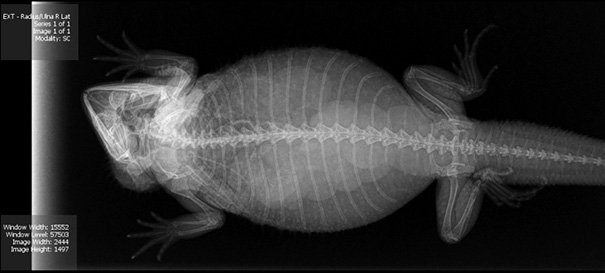

Итак, как выглядят рентгеновские снимки беременных животных:

черепаха